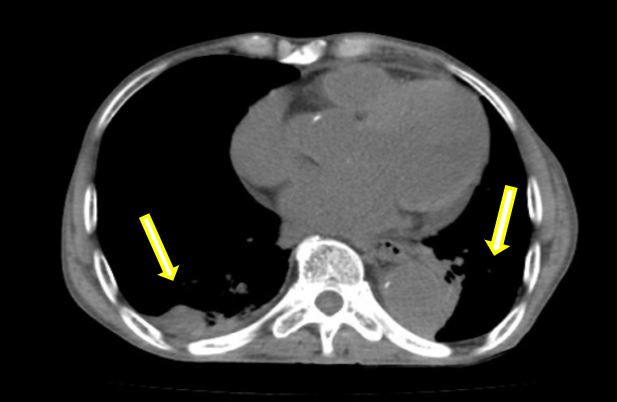

術(shù)后患者立即轉(zhuǎn)入重癥監(jiān)護(hù)病房(ICU),在李紅艷主任團(tuán)隊(duì)的精心管理下,患者一天后轉(zhuǎn)回血管外科病房,患者生命體征穩(wěn)定。根據(jù)術(shù)后CT復(fù)查結(jié)果,為解除肺部壓迫、緩解呼吸困難,術(shù)后胸心外科陳陽(yáng)天主任團(tuán)隊(duì)對(duì)患者進(jìn)行了胸腔穿刺引流,雙側(cè)胸腔引流出2000多毫升的不凝血性液體,這幾乎相當(dāng)于人體一半的血容量。經(jīng)過悉心的護(hù)理,患者術(shù)后恢復(fù)穩(wěn)定,呼吸、心率及全身狀況均得到了明顯改善,各項(xiàng)生化指標(biāo)平穩(wěn)恢復(fù),術(shù)后第十天,順利康復(fù)出院。

術(shù)前:雙側(cè)胸腔大量積血,雙肺受壓(箭頭示)

術(shù)后:經(jīng)引流后胸腔大量積液消失,肺部壓迫解除(箭頭示)